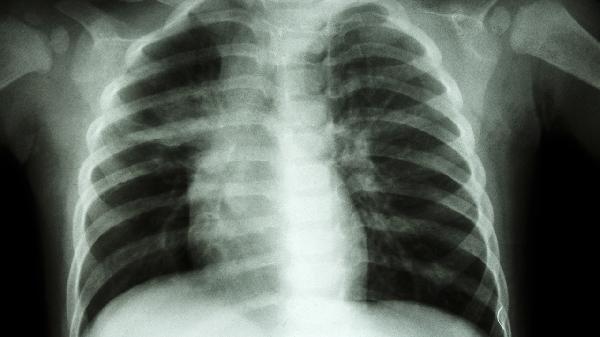

先天性肋骨发育异常如马方综合征、软骨发育不全等疾病也可导致肋骨外翻,这类患者多合并其他骨骼系统畸形,需通过影像学评估胸廓三维结构。极少数创伤后肋骨畸形愈合或胸壁肿瘤压迫也可能引发局部肋骨外翻,需结合病史鉴别诊断。

日常应注意避免单侧负重、过度挺胸等不良姿势,儿童需定期监测血清钙磷水平。若伴随呼吸困难、反复肺炎等症状,建议至胸外科或骨科进行CT三维重建检查,评估是否需手术矫正。哺乳期婴儿出现肋骨外翻时应排查先天性代谢疾病,并及时补充维生素D制剂。